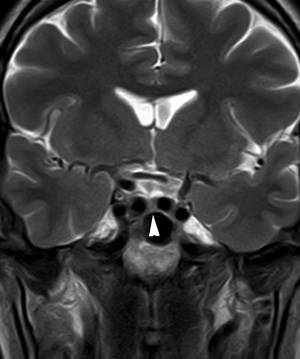

En general, el volumen y la forma de la glándula pituitaria varían con la edad, el sexo y las condiciones fisiológicas del individuo; así, por ejemplo, la hiperplasia pituitaria asociada al hipotiroidismo primario puede simular un adenoma pituitario. Algunas variaciones en la morfología corresponden al hecho que la glándula pituitaria debe acomodarse a la forma y volumen de la silla turca, lo que hay que tener presente al evaluar sus características (Figuras 6A, 6B y 7).

Figura 7. Corte coronal, secuencia T2w, muestra que la hipófisis ocupa la porción central de la fosa pituitaria (punta de flecha), con ambas arterias carótidas internas aproximándose a la línea media, lo que corresponde a una variante anatómica, que debe identificarse antes de realizar una cirugía por vía transesfenoidal.